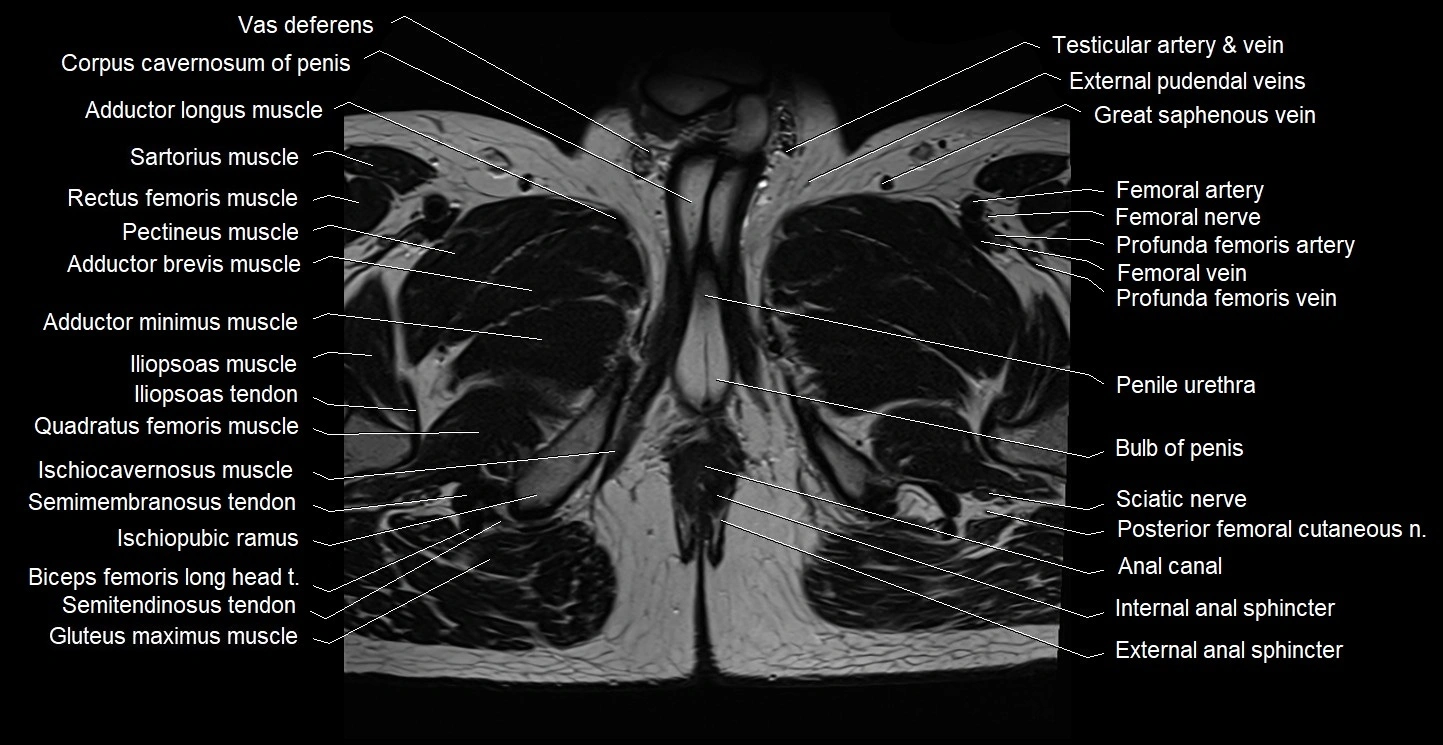

- Anal canal

- Bulb of Penis

- External anal sphincter

- Femoral artery

- Femoral nerve

- Femoral vein

- Gracilis muscle

- Iliopsoas muscle

- Iliopsoas tendon

- Internal anal sphincter

- Ischiocavernosus muscle (Male)

- Ischiopubic ramus

- Pectineus muscle

- Penile urethra

- Posterior femoral cutaneous nerve

- Pubococcygeus muscle

- Quadratus femoris muscle

- Rectus femoris muscle

- Sartorius muscle

- Sciatic nerve